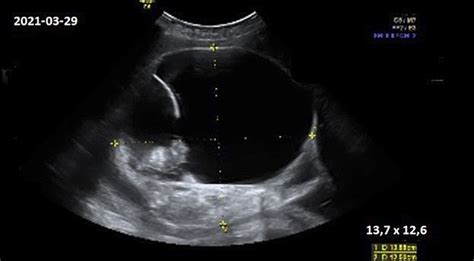

Dauguma embrionų 7 savaitę jau turi aktyviai plakančią širdį, nors ji dar labai maža (su ultragarsu galima pamatyti širdelės plakimą). Po truputį formuojasi kojos ir rankos, vystosi plaučiai, pasirodo bronchų užuomazgos, auga galvos smegenų pusrutuliai, vystosi akys ir nosies šnervės. Kaip ir 4-6 savaitę, taip ir 7-ąją išlieka tie patys nėštumo simptomai - pykinimas, krūtų jautrumas, svorio augimas/kritimas (šiek tiek numesti svorio nėštumo pradžioje yra normalu). Embrionas dabar yra maždaug avietės dydžio (1,6 cm).

Smulkūs plaukai, vadinami lanugo, pradeda dengti kūdikio kūną. Vaisius toliau sparčiai auga, o jo judesius jau galite pamatyti ultragarsinio tyrimo metu (jeigu tai ne pirmas nėštumas, judesius jau galite ir pajusti). Kūdikis jau moka aktyviai įkvėpti ir iškvėpto vaisiaus vandenis - taip treniruojami plaučių oro maišeliai. Vaisius taip pat nuryja šiek tiek vandenų ir taip mokosi gerti mamos pieną. Kūdikio oda padengta plonu plaukelių sluoksniu, kaulai sparčiai kietėja. Šiuo metu jau formuojasi kūdikio skonio receptoriai. Atlikti tyrimai rodo, kad jis jau gali jausti skonį. Iki šios dienos dažniausiai priaugama apie 2-2,5 kg svorio, nors tai priklauso nuo individualių organizmo savybių ir jūsų nėštumo.